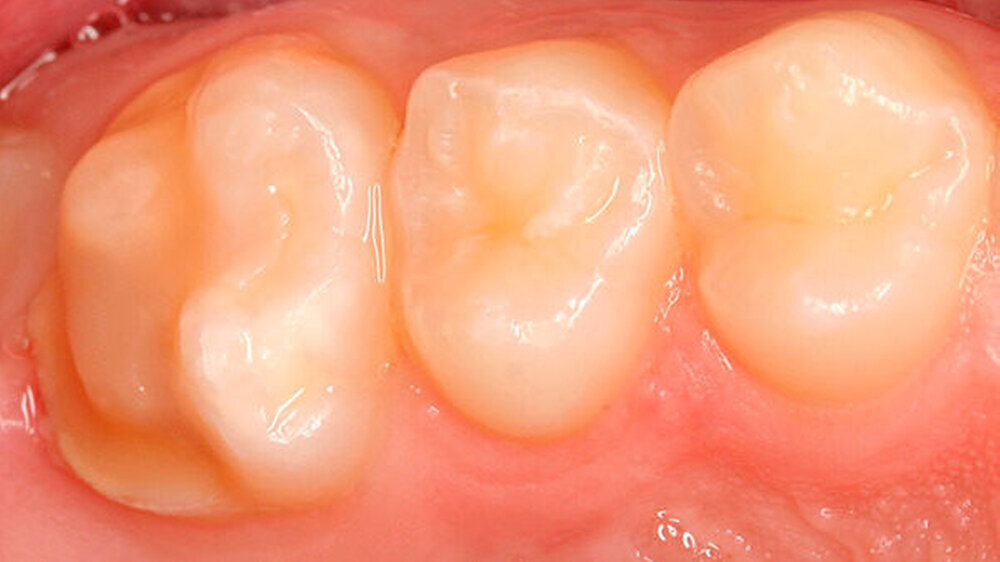

Zu all diesen Faktoren kommt hinzu, dass die nur geringen Erfolge der direkten Füllungstherapie einen häufigen Füllungsaustausch, Reparaturen oder Erweiterungen vorhandener Restaurationen bedingen [Lygidakis et al., 2010] (Abbildungen 3 und 4). Oft schon kommt es noch in der Durchbruchsphase zu ersten posteruptiven Schmelzeinbrüchen [Lygidakis et al., 2010], die meist nur eine temporäre Restauration erlauben.

Sämtliche betroffene Zahnhartsubstanz zu entfernen, was aber sehr oft das Kavitätendesign für eine direkte Füllungstherapie überschreitet (Abbildungen 5 und 6).

Die Entscheidung für eine Kavität, die von hypomineralisiertem Schmelz begrenzt bleibt, aber so die direkte Füllungstherapie aufgrund des Kavitätendesigns ermöglicht, sollte sorgfältig gegen die Entfernung sämtlicher betroffener Zahnhartsubstanz und erhöhter Wahrscheinlichkeit einer dauerhaften Restauration abgewogen werden. Dies kann nur für jeden Einzelfall entschieden werden.